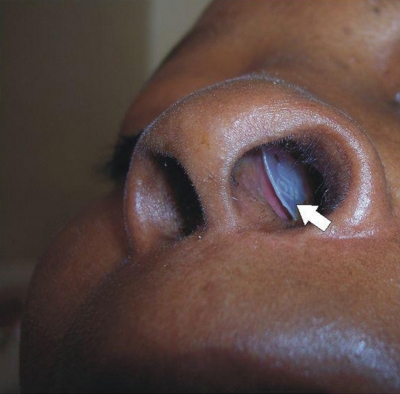

Case Report

J Otol Rhinol 2013, 2:1

10.4172/2324-8785.1000109

Case Report

J Otol Rhinol 2013, 2:1

10.4172/2324-8785.1000110